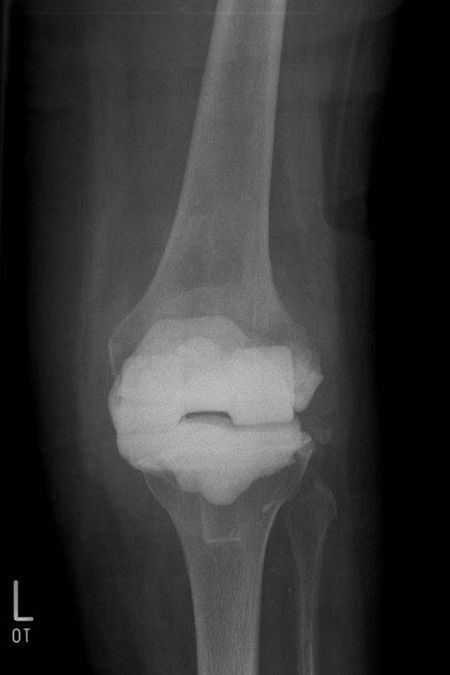

Eingesunkenes Tibiaplateau bei septischem Kniegelenk